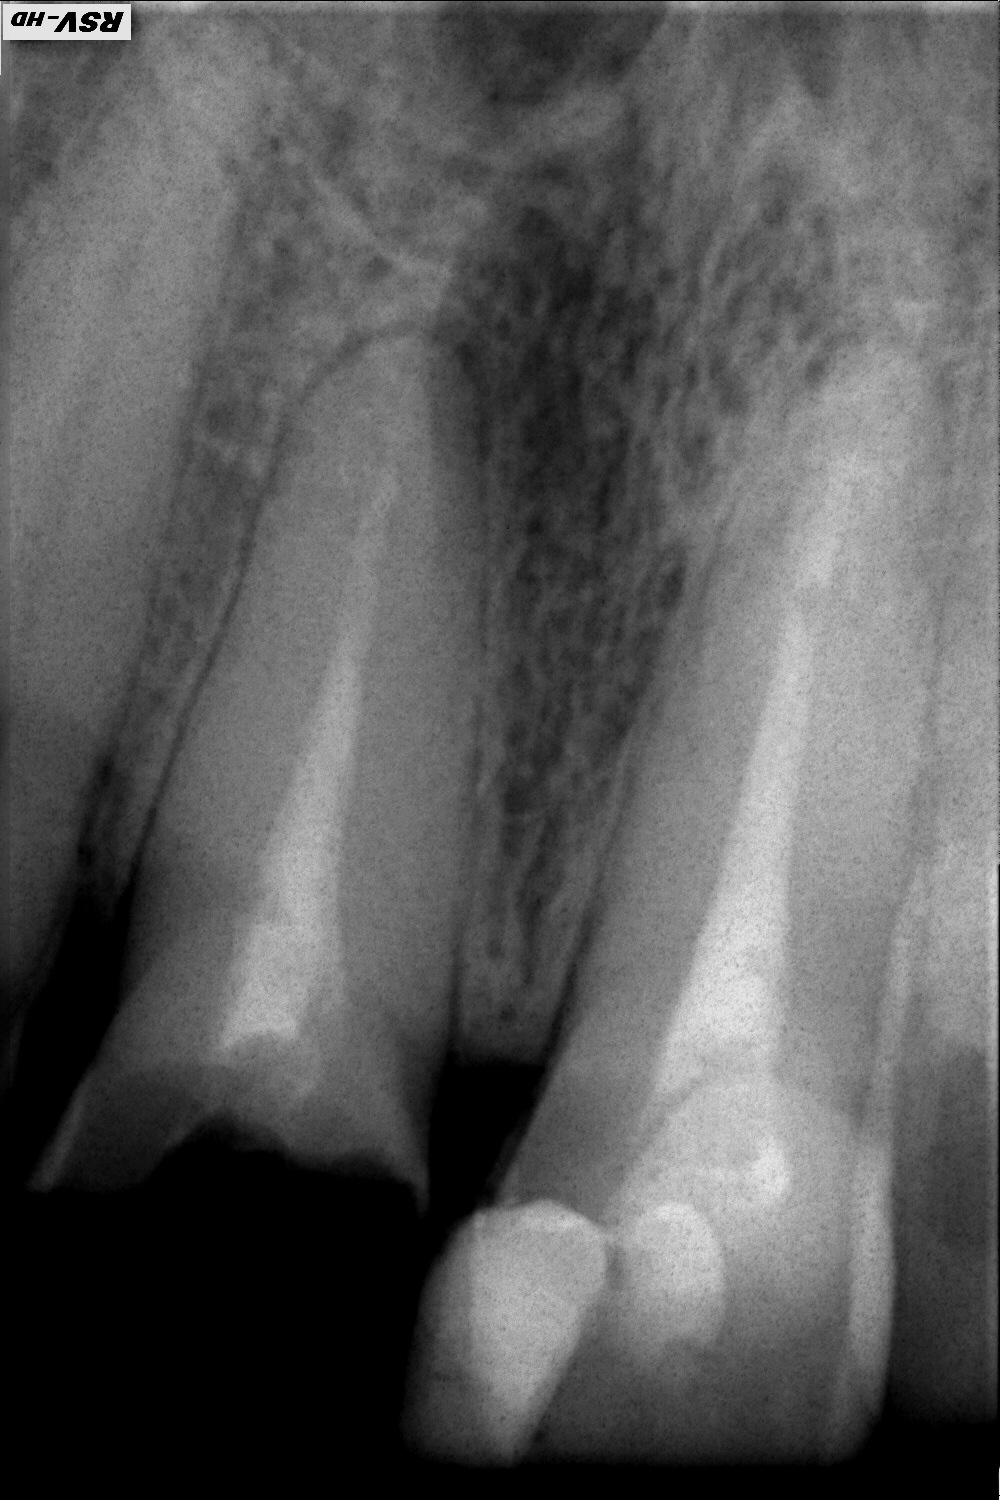

Около 14 лет назад у меня были депульпированы 21 и 11 зубы. За это время несколько раз меняла на них пломбы, состояние в целом устраивало. 14.08.2014 11 зуб обломился, осталось примерно 20% от коронки зуба. На консультации у ортопеда было рекомендовано протезирование керамической коронкой на с (ди)оксидом циркония на вкладке из сплава золото-платина с предварительным перелечиванием канала. Состояние до лечения на снимках:

• снимок 1 — прицельный,

Снимки показали наличие гранулемы на 11 зубе.

Далее канал 11 зуба был перелечен под протезирование с использованием Термофила. Снимки 3 и 4 сделаны в ходе лечения. На зуб была поставлена светоотверждаемая пломба (в качестве временной). В ходе лечения имел место выход пломбировочного материала за пределы канала, что видно на снимке, сделанном через несколько дней после перепломбировки канала (снимок 5). Лечащий терапевт уверила, что это нормальная ситуация, излишек материала со временем рассосется, а гранулема пройдет через 6 месяцев (возможно). Извините, если качество снимков не очень высокое! Снимки 2-5 пересняты с бумажных носителей.